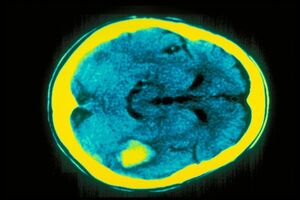

Como funciona o cérebro de um psicopata

O stress emocional na infância está muitas vezes na origem deste transtorno de personalidade. Mas a complexidade da psicopatia vai para além dos estereótipos.